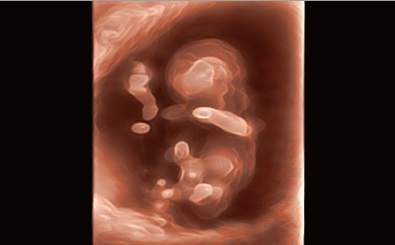

CLINICAL IMAGES

臨床影像

Abdomen